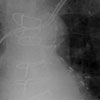

An ECG revealed a ventricular paced rhythm with right bundle-branch block (BBB) morphology and extreme axis deviation (A). The anteroposterior (AP) chest radiograph showed normal placement of the electrodes (B); however, the lateral film revealed a posterior deflection with the ventricular electrode entering the coronary sinus and resting in a contributory branch (C).

The differential diagnosis of paced right BBB morphology includes inadvertent LV lead placement, migration of the electrode into the LV (through a patent foramen ovale, atrial septal defect, or septal perforation), inadvertent coronary venous system placement, or right bundle-branch disease with anterograde block. Right BBB morphology during pacing requires further studies to determine the cause. As demonstrated in this case, the lat-eral chest radiograph is an essential part of the routine postoperative follow-up of patients with pacemakers. However, both AP and lateral films may be normal in patients with inadvertent coronary sinus lead placement.1 Echocardiography, which may be impractical, and intracardiac ECG, which is ideally performed in the electrophysiology laboratory immediately after implantation, also can be used to confirm correct electrode placement.